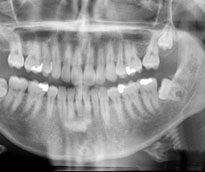

Oral Diagnoz ve Radyoloji